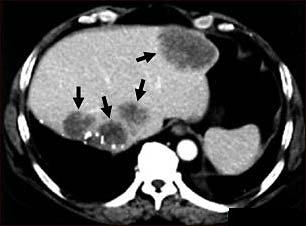

Screeningul cancerului hepatocelular